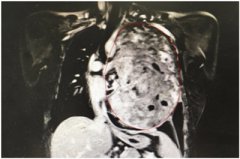

31岁妈妈胸腔内肿瘤长26厘米医生用手“摸除”

原标题:31岁妈妈胸腔内肿瘤长26厘米 医生用手摸除 肿瘤CT影像 手术中 图据四川省肿瘤医院 2019年母亲节过后的第3天,四川省肿瘤医院为一位31岁的年轻母亲摘除了一个胸腔巨大肿瘤。当完整的肿瘤组织从胸腔取出来时,现场所有医护人员都不断惊叹:该肿瘤最长